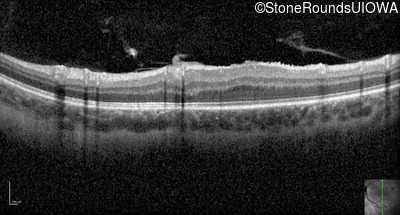

Optical Coherence Tomography - Right - 20/2000

Exemplar / OCT Stack